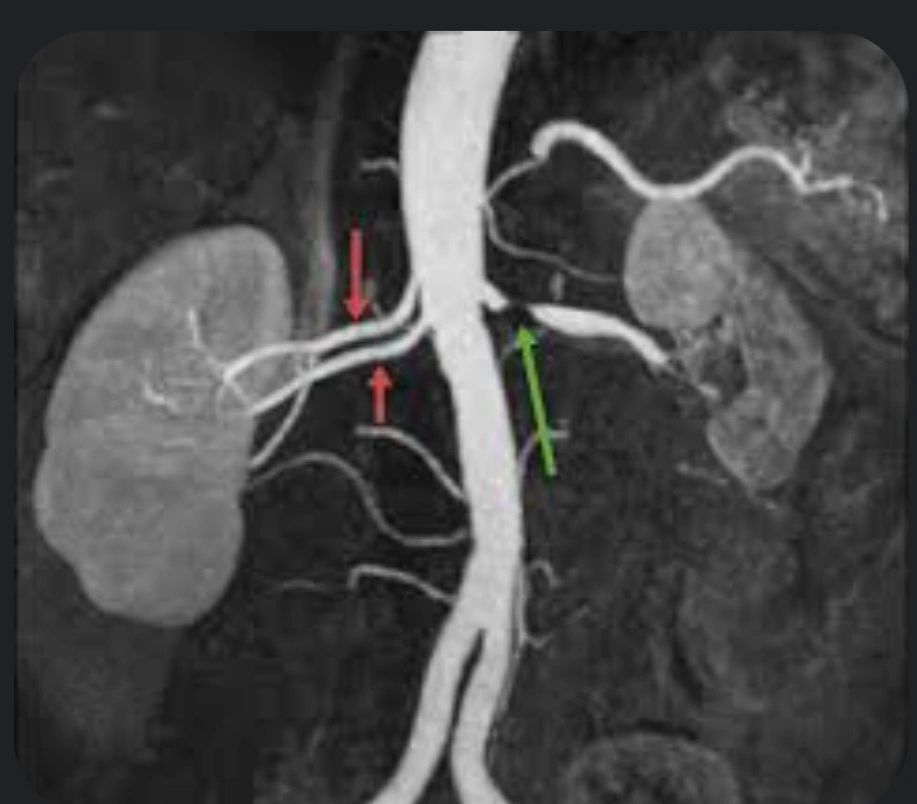

C. MR Angiography (MRA)

Sensitivity: 90–100% | Specificity: 85–94%

Excellent option in iodine allergy or moderate renal dysfunction

Limitation: Risk of nephrogenic systemic fibrosis with gadolinium in severe CKD

MR Angiography (MRA) Non-invasive 90–100 85–94 Good for CKD or contrast allergy